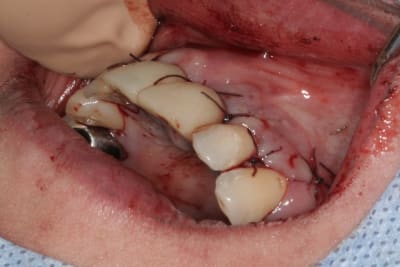

tien, ce matin, extraction de 24/25, curetage méticuleux, forage, comblement du gap, pose des 2 implants qui se sont bloqués à 50Ncm au CA sur les 3 ou 4 mm apicaux, pose des vis de cicat, sutures...35min....tranquille...

Purée, tu prends des risques énormes en fourrant ton bio oss puis en vissant les implants dans la masse de bio oss, de un, et sans membraner l'interface pilier implant, de deux...

Je suis peut-être vieux jeu mais c'est, à mon avis, dangereux d'un point de vue bactériologique.

c'est pas la première fois que je fais çà...;-)

et çà me donne plutôt de bons résultats

après tout...le périoste n'est-il pas la meilleure membrane?

par contre il faut veiller à avoir une bonne étanchéité au niveau des sutures...